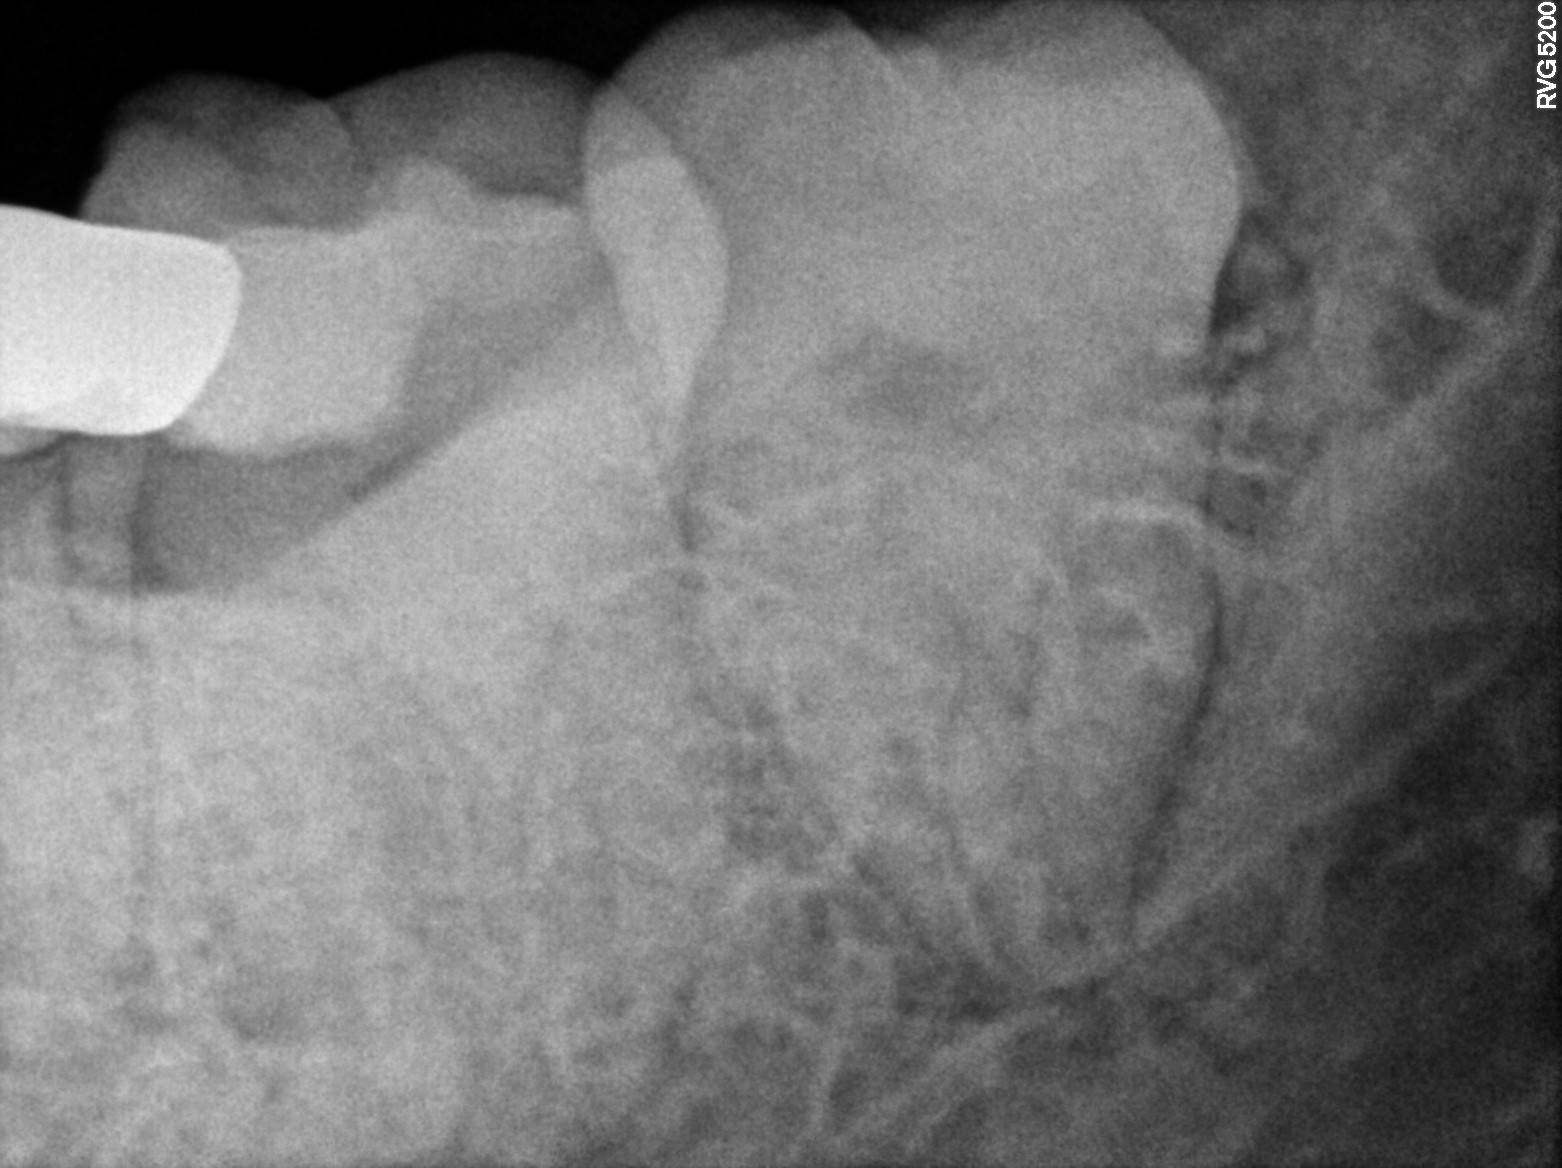

Dental Radiographs FHIR: DocumentReference · LOINC 24641-7

R38.jpg

24641-7